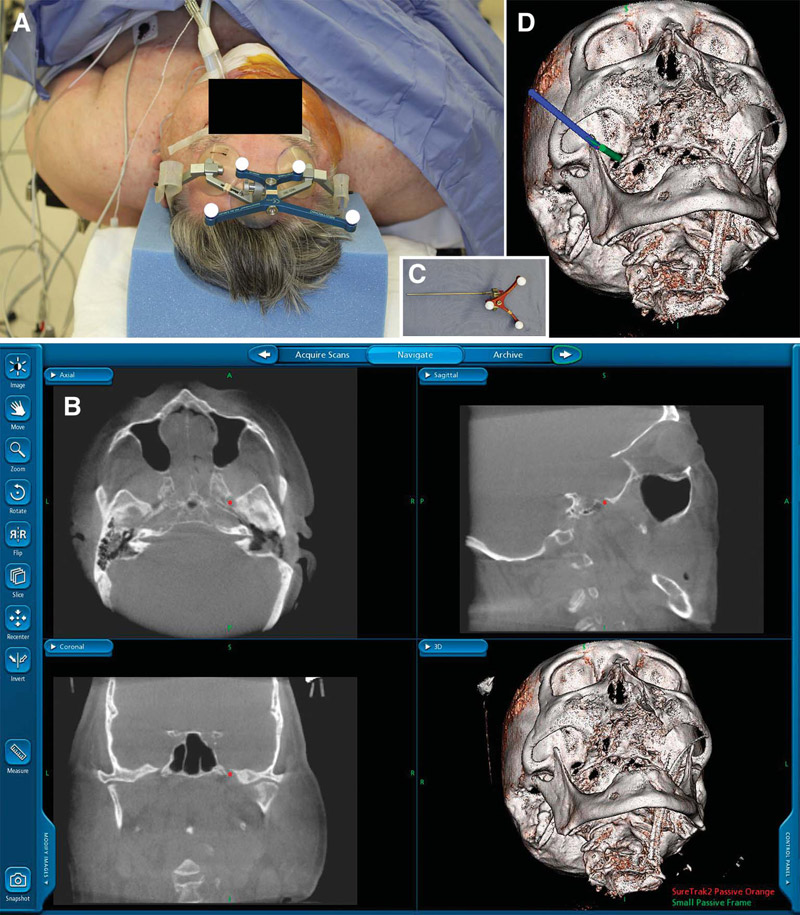

Αναφορικά με τις επεμβάσεις της σπονδυλικής στήλης, στην πράξη, το O-arm «ξεδιπλώνει» στο χειρουργό τη δύσκολη, και πολλές φορές «παράλογη», ανατομία της σπονδυλικής στήλης, χάρη στην προβολή της περιοχής σε 3 επίπεδα, σε πραγματικό χρόνο. Έτσι, η χρήση του O-arm εκμηδενίζει τις πιθανές τεχνικές δυσκολίες στις επεμβάσεις αυτές.

Το δυσκολότερο και πλέον χρονοβόρο μέρος της επέμβασης μπορεί πλέον να προβλεφθεί χρονικά με ακρίβεια, γεγονός που είναι δυνατό να μειώσει τον απαιτούμενο χρόνο του χειρουργείου έως και στο 1/3. Έτσι, παρέχεται η δυνατότητα ασφαλούς επέμβασης για ασθενείς που προηγουμένως ήταν υψηλού κινδύνου, καθώς και μείωσης της νοσηρότητας αυτών των επεμβάσεων.

Για τους ίδιους λόγους της πλήρους αποκάλυψης της ανατομίας, πλέον δεν προσπερνιούνται σπόνδυλοι που, λόγω της ανατομικής τους δυσκολίας παραλείπονται, ούτε και χρειάζεται να χρησιμοποιηθούν τεχνικές λιγότερο αποτελεσματικές, ώστε, τελικά, όλοι οι σπόνδυλοι να συμμετέχουν στη σπονδυλοδεσία με χρήση κοχλιών, με προφανώς εξαιρετικό τελικό αποτέλεσμα για τον ασθενή.

Επιπλέον, είναι γνωστός ο φόβος των ασθενών για παράλυση μετά από χειρουργείο στη σπονδυλική στήλη. Τώρα, πλέον, η ανασφάλεια για το νευρικό ιστό και ο φόβος του χειρουργού και του ασθενούς για κάποιου είδους παράλυση είναι, πράγματι, σε μηδενικό επίπεδο.

Χάρη στη μείωση του χρόνου επέμβασης και των πιθανών επιπλοκών του νευρικού ιστού, είναι δυνατή η επίτευξη μικρότερου χρόνου αναισθησίας, μικρότερης απώλειας αίματος, λιγότερων μεταγγίσεων, μικρότερης έκθεσης σε λοιμώξεις, βραχύτερης παραμονής στην Εντατική Μονάδα μετά το χειρουργείο και, γενικότερα, σημαντικής μείωσης του stress του ασθενούς, με αποτέλεσμα μικρότερη νοσηρότητα από μη χειρουργικά προβλήματα.